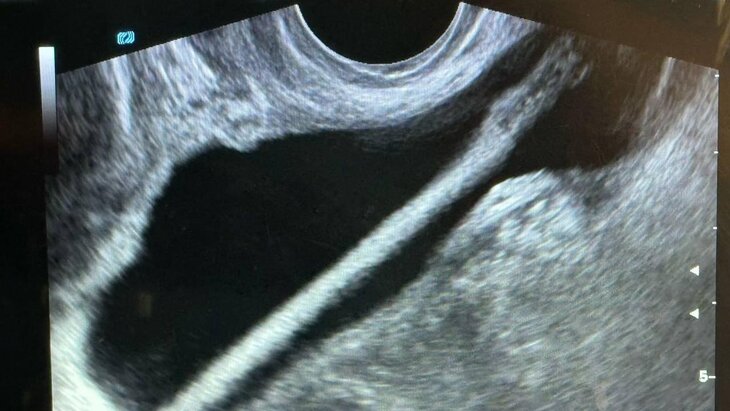

Заведующий отделением Петр Сысоев рассказал, что после проведения УЗИ пациентке была проведена эндоскопическая операция, в ходе которой инородное тело удалили без осложнений. Сейчас женщина уже выписана домой.